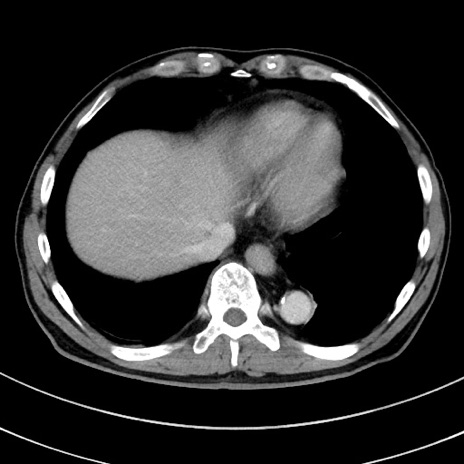

冠状断像

【症例】 60歳代男性

【主訴】 黒色吐物

【現病歴】 4日前から嘔気自覚、2日前の朝食後にも嘔気あり、自分で手で嘔吐反射起こし嘔吐したところ血が混ざっていたため受診。

【既往歴】 5年前汎発性腹膜炎を伴う急性虫垂炎で手術、高血圧、前立腺肥大症、高脂血症

【身体所見】 腹部正中に手術癩痕あり 腹部平坦・軟圧痛なし膨満感あり

【データ】WBC 8400、CRP 4.54